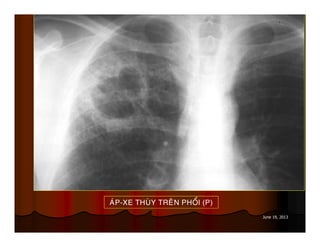

AÙP-XE THUØY TREÂN PHOÅI (P)

June 19, 2013 AÙP-XETHUØY TREÂN PHOÅI (P)